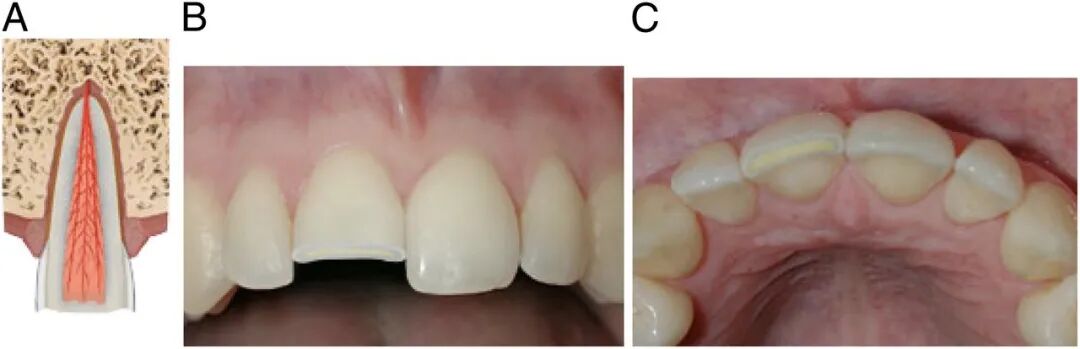

牙齿撕脱

科普推荐的泡牛奶啊、泡口水啊,都是针对恒牙的急救措施。

恒牙的撕脱是所有牙齿伤害中最严重的,而且首选治疗方法确实是立即再植。

为保证恒牙能成功接回去,磕掉牙第一时间家长应该这么做:

1、首先,先找到摔掉的牙,捏住牙冠部(注意不是牙根);

2、如果恒牙掉地上沾土了,千万别擦,在冷流动水下短暂冲洗10秒,然后重新放回牙槽中,再让孩子咬住干净棉球或毛巾将牙齿固定住,然后去急诊。

3、如果无法立即植入牙齿,则应将其存储在有助于保持牙周膜纤维细胞活力的介质中。比如泡在冷牛奶或生理盐水中,实在不行含在舌下,或者往杯子里吐口水,把牙齿泡进去也可以。

但是别把牙齿泡水里,因为水会引起牙周膜纤维细胞的渗透性溶解。

4、以上所有动作都要快,牙齿口外干燥超过60分钟,牙根细胞就不容易存活了。